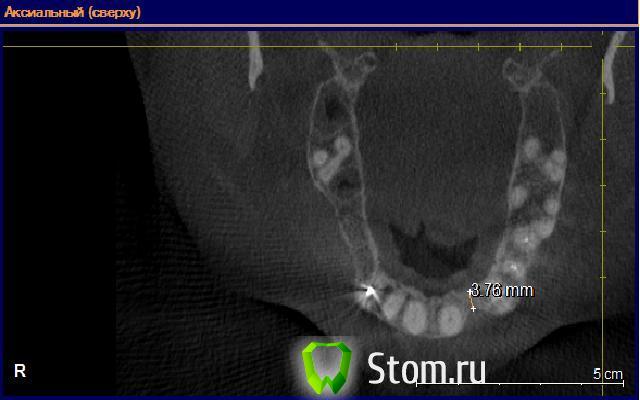

alexandr_spb Опубликовано 3 февраля, 2012 Поделиться Опубликовано 3 февраля, 2012 планирую поставить 3.0 биогоризонт в позиции 22. но вот кость 2-3 тип и толщина 4.3 всего . ломаю голову что лучше горионтал или сплит от мейсингера... КТ постараюсь завтра скинуть Ссылка на комментарий

alexandr_spb Опубликовано 6 февраля, 2012 Поделиться Опубликовано 6 февраля, 2012 Добрый день коллеги! составляю план . поправте если что не правильно говорю и делаю.22 зуб - планируется имплантация 3.0 биогоризонт с предварительной аугментацией альвеолярного отростка по методике split control+биоосс+своя костная стружка+мембрана. кт прилагаю. Пациент гарантийный по этой причине костные блоки пока не рассаматриваются. Ссылка на комментарий

GIC77 Опубликовано 11 февраля, 2012 Поделиться Опубликовано 11 февраля, 2012 Добрый день коллеги! составляю план . поправте если что не правильно говорю и делаю.22 зуб - планируется имплантация 3.0 биогоризонт с предварительной аугментацией альвеолярного отростка по методике split control+биоосс+своя костная стружка+мембрана. кт прилагаю. Пациент гарантийный по этой причине костные блоки пока не рассаматриваются.В вашем случае, вполне достаточно места для расщепления гребня Ссылка на комментарий